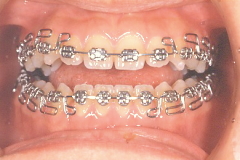

治療途中経過

![]()

治療終了時

| ■主訴/咬み合わせが深く、下の歯が見えない ■診断名あるいは主な症状/過蓋咬合 ■年齢/12歳11か月 ■治療に用いた主な装置/スタンダードエッジワイズ法、マルチブラケット装置 ■抜歯部位/上顎・左右4番 ■治療期間/3年1か月・通院回数37回(月に一度)、保定2年・通院回数8回(3ヶ月に一度) ■治療費概算(自費)/約80万円(税込) ※ 矯正歯科治療は公的健康保険の対象外の自由(自費)診療となります。 ※ 治療費用は改定しています。現在の治療費は矯正費用ページをご参照ください。 |